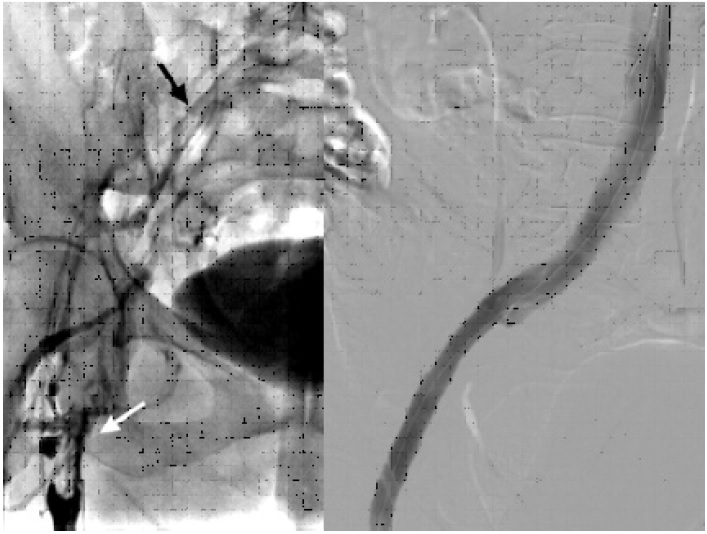

The patient underwent a computed tomography (CT) scan that reported thrombosis of the left internal jugular vein, with occlusion of the left brachiocephalic and subclavian veins (shown in Fig. 1). There was no evidence of collections/abscesses. A brief transthoracic echocardiography was performed in the ER, which rose the suspicion of thrombus/endocarditis. The subsequent transesophageal echocardiogram documented a thrombus adherent to the pacemaker leads. There was an equivocal image of vegetation. Blood cultures, blood panel with C-reactive protein (CRP) and procalcitonin (PCT) were collected. The patient was also scheduled for a repeat CT for evaluation of pulmonary embolism.

Imagen de estudio dividida en 2

Fig. 1 Left. Computed tomography angiography axial section evidencing aortic bifurcation (black arrows), behind the iliocaval junction (white arrow). Right. Sagittal section shows compression by the left hypogastric artery (black arrow) causing external iliac vein thrombosis (white arrows).

Fig. 2 Left. Initial phlebography showing thrombosis from the proximal femoral vein (white arrow), which rechannels with low flow at the common iliac vein level (black arrow). Right. Final phlebography after stent placement showing absolute permeability of the iliac axis